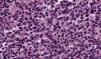

Se trata de un varón de 86 años diagnosticado de síndrome mielodisplásico (SMD) hacía dos años. Consultaba por dos carcinomas basocelulares en la sien izquierda y el ala nasal derecha. Se realizó extirpación de ambos y cierre mediante sutura directa y plastia del surco nasogeniano, respectivamente. A las pocas horas de la cirugía el paciente acudió a Urgencias por presentar un sangrado activo difuso en ambas heridas con aparición de un gran hematoma en el área de la plastia. En la analítica destacaban: leucocitos 12.200/μl (> 10.000, neutrófilos 31,2%, linfocitos 21,3%, monocitos 43,6%), hemoglobina 11,7g/dl (< 13), plaquetas 65.000/ μl (< 150.000) y creatinina 1,5mg/ dl (> 1,3) siendo la coagulación, el perfil hepático y LDH normales. Al mes de la cirugía apareció en la plastia, previamente perfectamente cicatrizada, un nódulo asintomático, de rápido crecimiento junto a la infiltración progresiva de la zona inferior de la cicatriz y ulceración (fig. 1). Las biopsias tanto del nódulo como de la cicatriz infiltrada evidenciaban una proliferación neoplásica difusa en la dermis y en el tejido adiposo, constituida por células mononucleares de mediano tamaño, de morfología redondeada-oval, citoplasma eosinófilo y núcleo basófilo (fig. 2). El estudio de inmunohistoquímica (IHQ) fue positivo para mieloperoxidasa (MPO), CD68, CD43 y focalmente para CD34, diagnosticándose de SM (fig. 3). Simultáneamente el paciente presentó una progresión clínica de su enfermedad hematológica a LMA M4 (clasificación FAB). Se inició tratamiento paliativo con tioguanina, pero finalmente el paciente falleció en tres semanas.

El diagnóstico histológico del SM requiere un alto índice de sospecha, y puede pasar desapercibido si no existe el antecedente de LMA. Se observa un infiltrado neoplásico denso en la dermis y la grasa, con tendencia a disponerse en torno a vasos y anejos, sin epidermotropismo, y es característico que la dermis papilar esté respetada (zona Grenz). El aspecto citológico es muy variable, dependiendo del origen y grado de maduración celular. La IHQ es fundamental para el diagnóstico y se recomienda que incluya CD68, MPO, CD43, CD3, CD20 y cloracetato esterasa2,3.